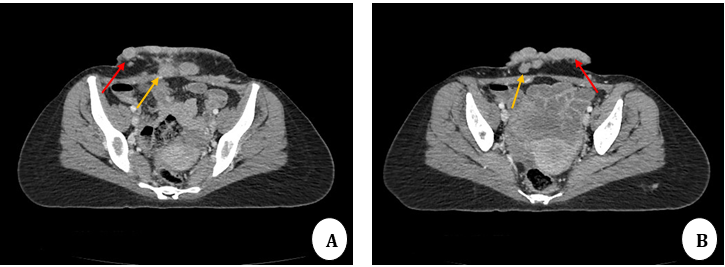

FIGURE 1 A & B: Contrast-enhanced CT scan axial images: Multiple enhancing cutaneous (red arrows) and subcutaneous nodules (yellow arrows) are noted in the lower anterior abdominal wall.

Contrast-enhanced CT of the chest, abdomen, and pelvis revealed: 1. Multiple enhancing cutaneous and subcutaneous nodules in the lower anterior abdominal wall (Figure 1); 2. Bilateral multiple enhancing breast lesions with signifi cant internal vascularity on ultrasound (Figure 2A); 3. Bilateral pulmonary soft tissue nodules (Figure 2B); 4. A hypodense lesion in the left hepatic lobe (Figure 2C); and 5. Lytic lesions involving multiple bones (Figure 2D) findings consistent with metastatic spread.